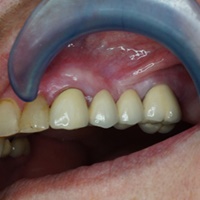

Wskazania do wykonania resekcji zębów 21, 22. Prawie niewidoczna blizna pooperacyjna.